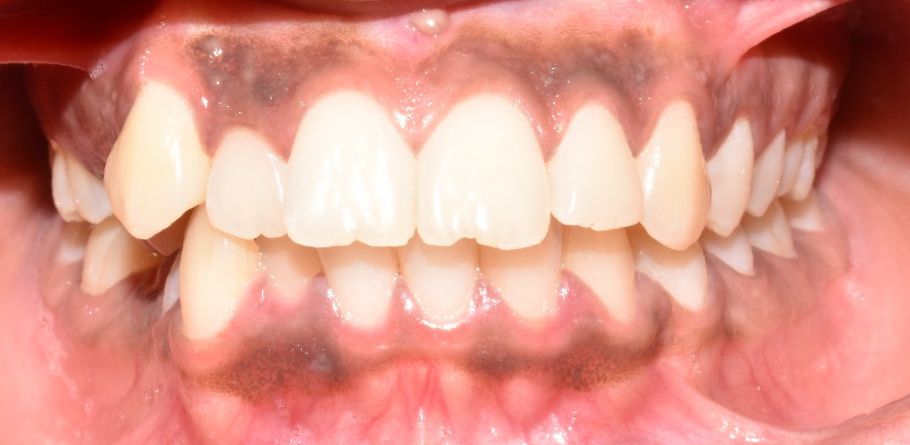

Before & After Results

At Aline Dent, we take pride in delivering visible and lasting improvements in our patients’ smiles. Our before-and-after results highlight the effectiveness of modern dental treatments combined with personalized care. This gallery showcases real dental cases treated at our clinic, giving you a clear idea of how different dental concerns can be corrected with the right treatment approach.

From minor corrections to complete smile enhancements, these teeth transformation results demonstrate how professional dental care can improve both oral health and appearance. Our experienced dental team carefully evaluates each patient’s needs and creates customized treatment plans to achieve natural, healthy, and confident smiles.

In this gallery, you will find a variety of smile makeover cases, including treatments for crooked teeth, gaps, discoloration, damaged teeth, and other common dental concerns.